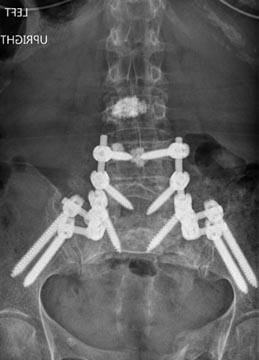

73 year old woman with osteoporosis who fell and fractured her pelvis. She was unable to walk and developed lumbopelvic dissociation (seperation of the spine from the pelvis and lower half of the body) from an unstable sacral fracture and displacement.

Lumbopelvic fixation with prophylactic cement augmentation and patient was immediately able to walk again.